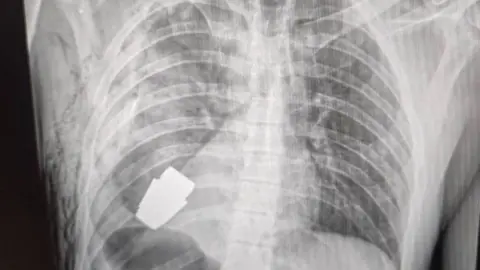

Facebook/Ukraine medical force commandAn unexploded grenade has been removed from the chest of a Ukrainian soldier.

Photos on the Facebook page of Ukraine's armed forces medical service show an X-ray of the explosive close to the serviceman's heart, and another of the surgeon holding the device.